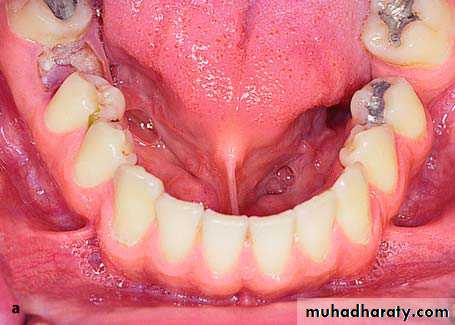

Multiple ExostosesThese are rare asymptomatic bony excrescences, usually localized at the buccal surface of the maxilla and mandible. The causes are unknown, although some people suggest that they may be due to bruxism as well as chronic irritation of the periodontal tissues. No therapy is usually required, except for those cases where, due to the large size of the exostoses, severe esthetic and functional problems are created.

Extremely large multiple exostoses in the maxilla with a multilobular and irregular shape